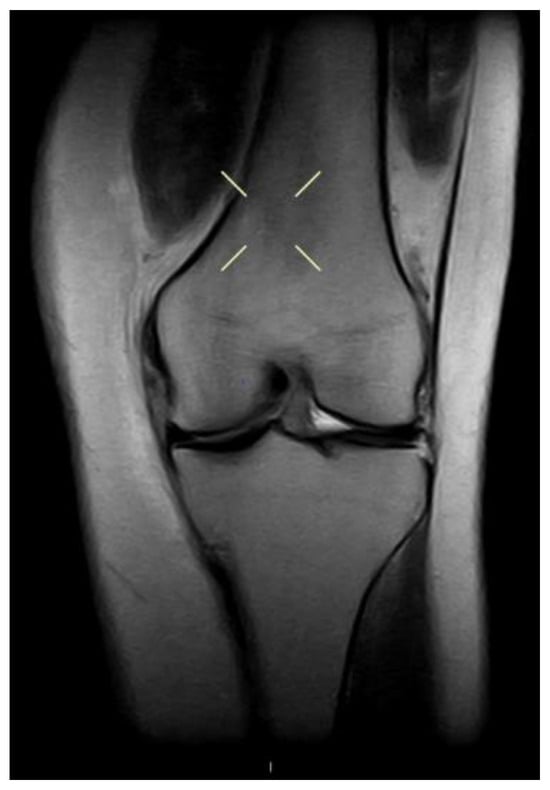

4.5. Laximeter Imaging Analysis Software